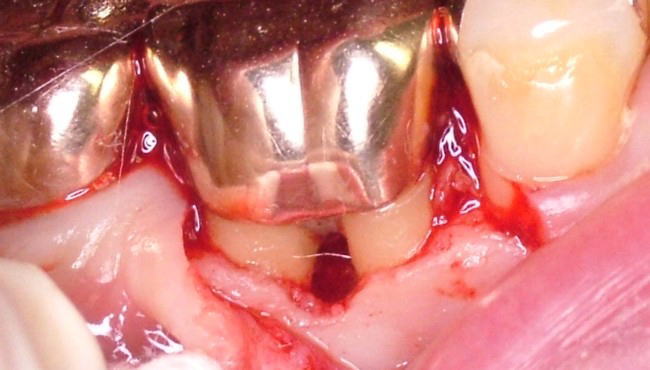

根分岐部病変が一旦発症してしまうと、その治療はなかなか困難です。多くの場合大臼歯部で起こるため、その位置的な事情や歯根の懈怠の複雑さなどから、正確な診断、術者側の施術、患者さんの管理などいずれも困難を極めます。

治療法としては様態に応じて、スケーリング・ルートプレーニング・分岐部入り口の整形によって磨きやすい形態を作る→歯槽骨の整形→歯根に対する処置(いずれかの根を抜歯する・複数の根の間を分割するなど)やトンネルの形成などの処置があります。 また「再生療法」として薄い皮膜を用いて歯槽骨の再生を誘導する『組織再生誘導法(GTR法)』や特殊な薬剤を用いる『エムドゲイン法』などがあります。 |